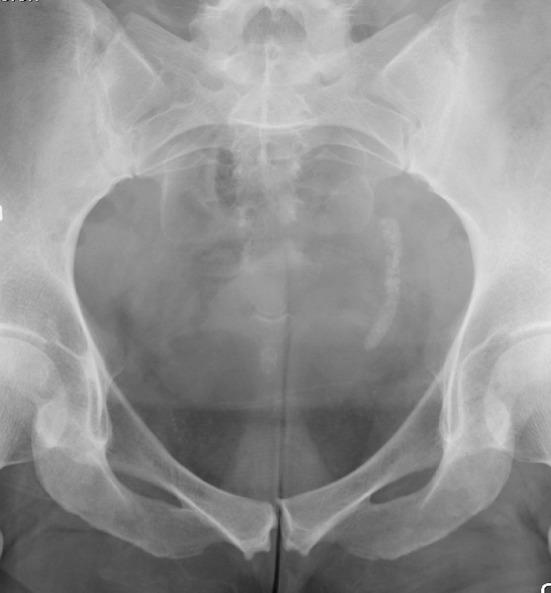

It is well recognized that the popularity of extracorporeal shock wave lithotripsy (SWL), despite its non-invasive character, has decreased during recent years. This is partly explained by the technological achievements in endoscopy and urologists' enthusiasm for such procedures. Another explanation is that many urologists have been insufficiently successful with SWL. The latter effect might to some extent be a result of the performance of the lithotripter used, but in too many cases, it is evident that the principles of how shock wave lithotripsy should be carried out are poorly applied. The purpose of this article is to emphasize some important aspects on how SWL best should be used. Based on decades of experience, it stands to reason that success with SWL does not come automatically and attention has to be paid to all details of this technique.